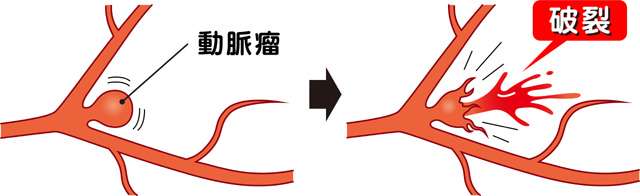

脳動脈瘤は脳の動脈の一部がコブのように膨らんだもので、破れやすくなっています。破裂した場合、くも膜下出血という非常に危険な状態となります。